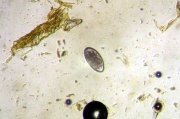

ჰემონქუსი (haemonchus; ბერძნ. haima სისხლი + onkos შევსებული) ნემატოდას გვარი; მიეკუთვნება Trichostrongylidae-ს ოჯახს, Strongylata-ს ქვერაზმს. მცოხნელი ცხოველების პარაზიტი. ლოკალიზობს კუჭ-ნაწლავის ტრაქტში.